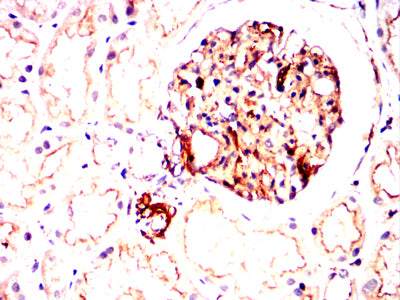

Immunohistochemical analysis of paraffin-embedded human kidney tissues using ATM mouse mAb with DAB staining.

-

Immunohistochemical analysis of paraffin-embedded human gastric cancer tissues using ATM mouse mAb with DAB staining.

Immunohistochemical analysis of paraffin-embedded Mouse spleen tissues using ATM mouse mAb with DAB staining.